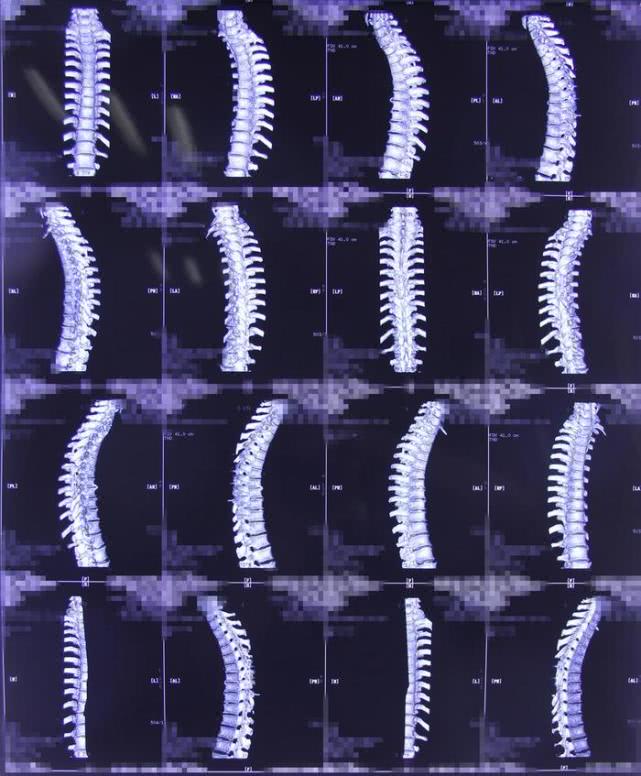

术后影像学资料

胸5-7